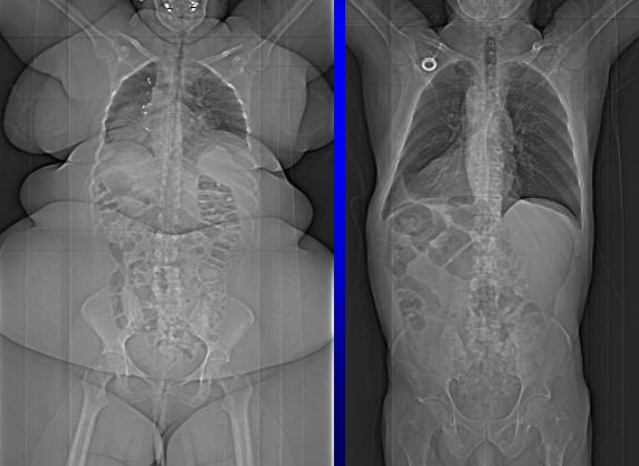

18.09.2016 - 11:20:10 <anon> thick bones syndrome

18.09.2016 - 11:33:30 <anon> how the fuck can those bones even take that pressure and weight... they should crack

18.09.2016 - 12:03:32 <anon> Hah. oikealla puolella joko käännetty kuva tai sitten situs inversus. Ei tilanne muutenkaan hyvältä näytä: atelektaasia keuhkoissa, suurentunut maksa ja venyttynyt koolon.

18.09.2016 - 15:59:24 <anon> eikös oikeella oo muutenki mies? ainaki vahvemmat luut

18.09.2016 - 21:07:50 <anon> the one on the right is a man

19.09.2016 - 01:15:45 <anon> "you don't get it. i'm big-boned. stop fat-shaming."